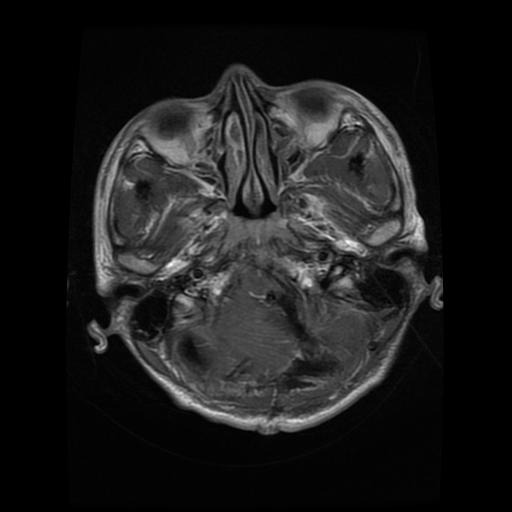

MediScan AI is a web-based application that takes in medical images (like X-rays or CT scans) and uses deep learning models to detect anomalies. It visually highlights the region of concern and provides a confidence score for the prediction, offering valuable insights to users.

• We trained a U-Net segmentation model using PyTorch to identify regions of interest in medical scans.

• 🧠 Built a Working Prototype: We successfully developed a functional web app that can analyze medical images and highlight potential abnormalities using deep learning.